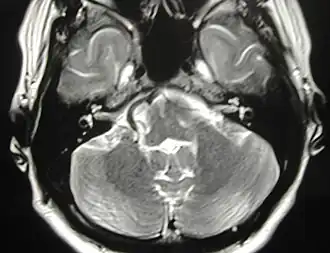

Аксиальная МР-томограмма. Конфликт артериального сосуда с правым лицевым нервом. Клиническая картина: правосторонний гемифациальный спазм.